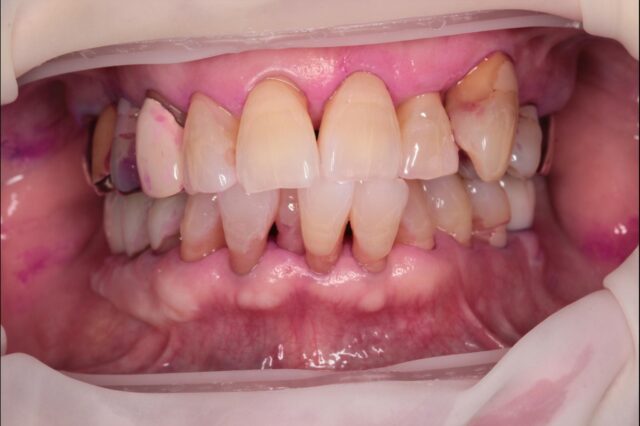

口腔内全体の治療

| 症状 | 他院でインプラントはできないと言われたので、インプラントして欲しい 歯並びも悪いので何とかならないか |

| 治療法 | 左上1インプラント治療 右上1審美補綴治療 矯正治療 |

| 費用 | 全体約106万円 |

| 通院回数 | 2年半 1,2回/月 |

| 備考 | 全体で問題が起こり機能が失われた状態をトータルでマネジメントし元あった理想に近い形に戻すことを行なっているが、これにはかなりの時間と費用がかかり、大変な治療に耐えていただく必要がある。 また全ては修復物や補綴物やインプラントで見た目と噛む機能を整えているに過ぎず、実際には歯が再生したわけではない。強度の落ちている歯をよく噛める形に整えるという事は、歯が壊れる可能性も同時に上げることになる。つまり施した治療が必ずしも一生保つという事ではない。 よって可能な限りこの状態を長く保つことが出来るよう、治療後は定期的なメンテナンスと、ナイトガード(寝ている間の歯軋りや食いしばりなどの自身でコントロールできない過剰な力から歯を守るマウスピース)の装着が必須となる。 |